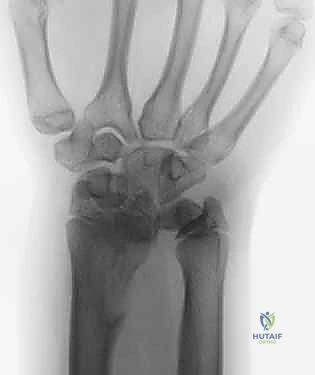

2. التصوير الشعاعي (X-Rays)

تُعد الأشعة السينية ضرورية لقياس "التباين الزندي". يتم أخذ صور بأوضاع محددة (مثل وضعية القبضة المشدودة) لإظهار أقصى درجات الضغط بين الزند والرسغ.